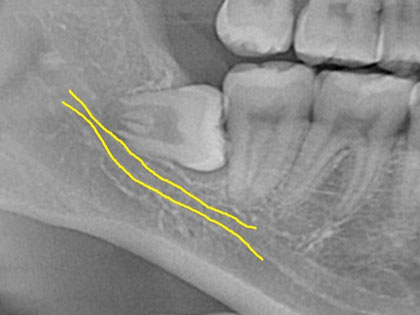

親知らず抜歯症例

親知らず抜歯症例1

親知らずを抜きたいとの事で来院、治療を希望された患者様の症例になります